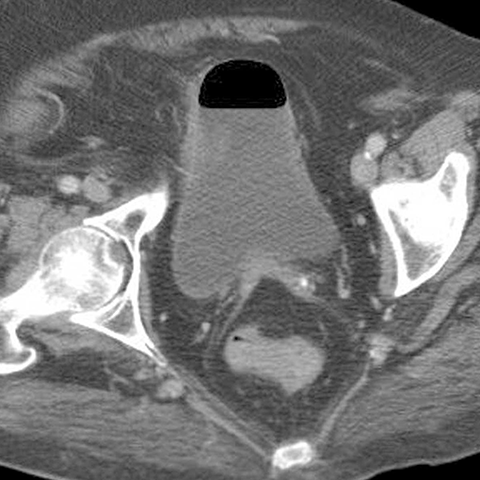

65 year-old male presents with fever and LLQ pain. [5 of 5]